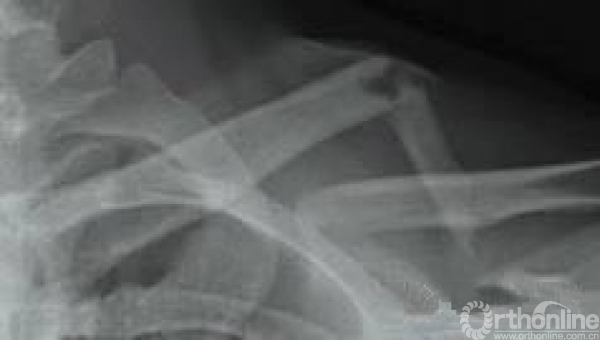

从胸腔里面的重建CT我们可以看到,锁骨下动静脉经过锁骨和第一肋骨之间穿过。